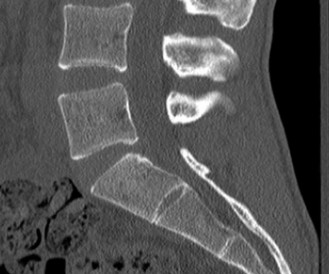

Initial trauma radiographs demonstrated a loss of anterior and middle column height at L1, with a focal kyphotic deformity. However, plain films are vastly insufficient for definitive surgical planning in thoracolumbar trauma. A high-resolution, fine-cut Computed Tomography (CT) scan of the entire spine was obtained. The CT images confirmed an L1 burst fracture with severe comminution of the vertebral body. Sagittal and axial reconstructions revealed 50% canal compromise secondary to a large retropulsed bone fragment originating from the posterosuperior aspect of the L1 vertebral body. Furthermore, the CT demonstrated 25 degrees of segmental kyphosis measured from the superior endplate of T12 to the inferior endplate of L1.

A critical finding on the axial CT slices was a vertical, split fracture propagating through the L1 lamina. This is a highly significant morphological feature. A lamina fracture in the setting of a burst fracture with retropulsion strongly correlates with a dural tear and potential entrapment of the cauda equina nerve roots. When the vertebral body bursts posteriorly, the pedicles are driven outward, and the lamina fractures as the spinal canal attempts to expand to accommodate the retropulsed bone. If the dura is lacerated, nerve roots can herniate through the dural defect and become incarcerated in the laminar fracture site.